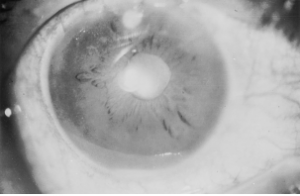

Intraocular nocardiosis is rare. Reported Nocardia endophthalmitis are commonly from haematogenous (endogenous) spread of the organism and occasionally exogenously. Hematogenous spread occurs to the eye, resulting in choroidal abscess or endophthalmitis.[19][20] The clinical picture consists of a large, yellow choroidal lesion with hemorrhage in the overlying retina. Chorioretinal lesions are usually located in the central and paracentral regions. Retinal thickening and exudative retinal detachment can occur, as well as optic nerve head elevation. Nocardia endophthalmitis can present with a hypopyon and no posterior findings.[21] Endogenous Nocardia endophthalmitis is most commonly unilateral. Bilateral nocardial infections have been reported in cases of pulmonary Nocardia asteroides infection and in those with hypogammaglobulemia.[22] Exogenous Nocardia can occur after cataract surgery, penetrating injury and trabeculectomy. There is anterior segment inflammation and hypopyon. Yellowish-white nodules can be seen over the iris (Figure 3) and puffball opacities may be visible in the anterior vitreous.[23]